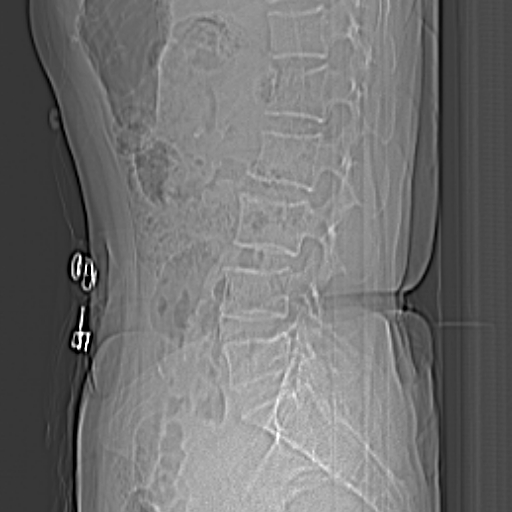

骨窗: